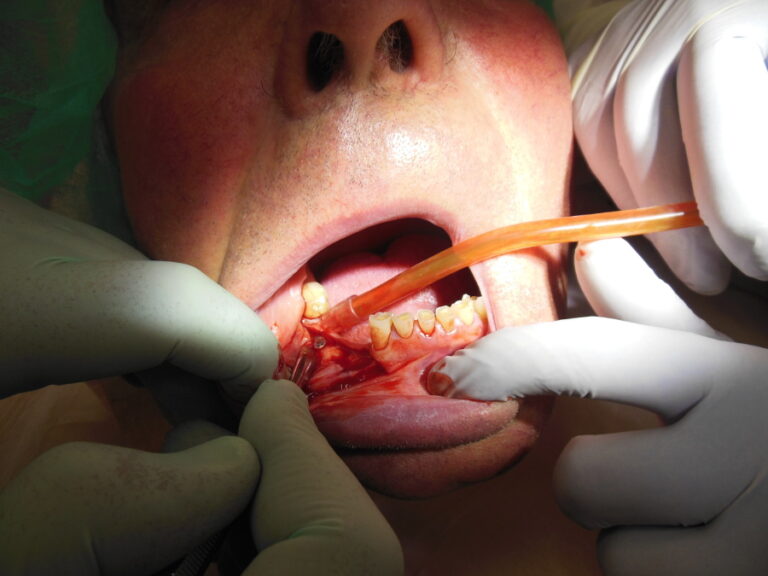

Przykłady implantologii

Zastosowanie implantoprotetyki w przypadku gdy klasyczna protetyka nie sprawdza się.